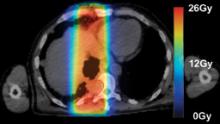

Radiation therapy is an important clinical option for the alleviation of pain and suffering for cancer patients and is used for palliative treatments to prevent pathologic bone fractures or tumor-induced obstructions, bleeding and pain that is resistant to other treatments.

However, standard palliative radiation therapy treatment techniques often offer poor conformality and expose large volumes of normal tissues to radiation-induced toxicities, causing significant side effects for an already ill patient with a limited life expectancy.

Treatment planning is a critical component of a patient’s road toward an optimal outcome when dealing with cancer. Whether the ultimate goal is palliative or a total cure, treatment planning always aims to provide just enough dose to a targeted area to eradicate the cancer, while sparing nearby tissue or organs.